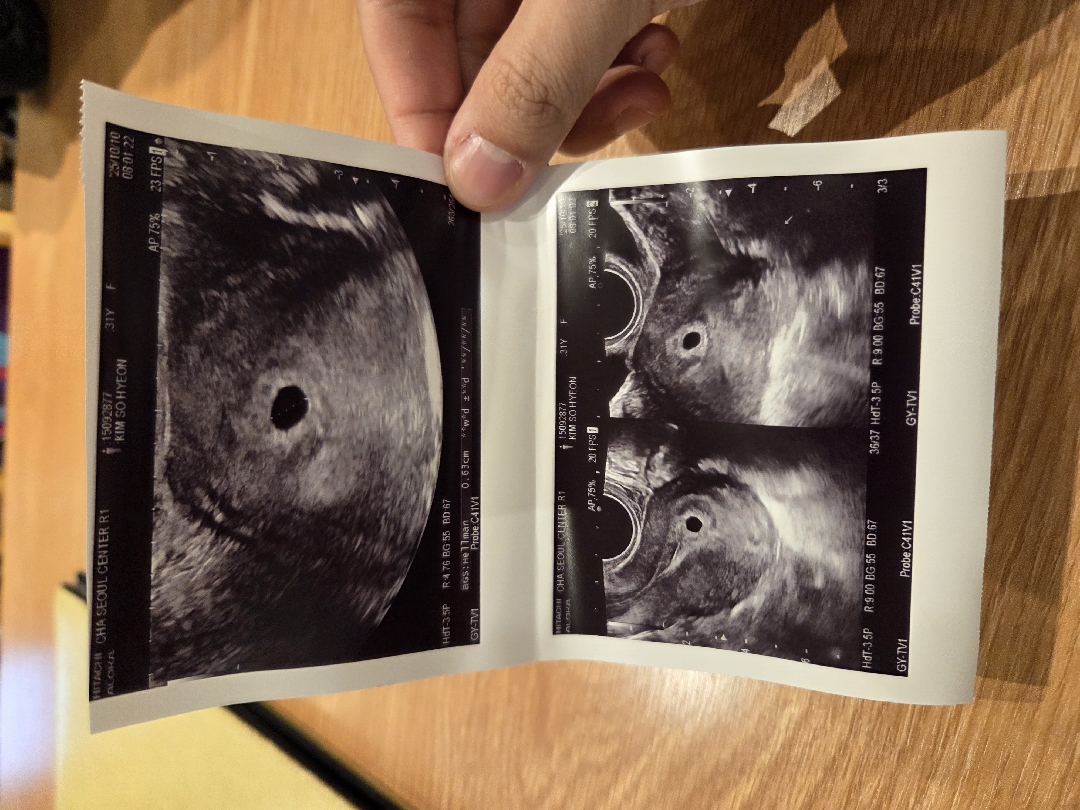

4주4일차인데 난황이 안보이는거 정상이겠죠...?

시험관 2차 5일 동결배아 후 연휴 기간에 임신테스트기 2줄 확인하고 오늘 병원가서 초음파 사진 받았어요. 아기집은 0.63cm로 확인됐는데 난황은 아직 안보인다고 하네요. 원래 이시기에는 안보이는게 일반적이겠죠??? 마지막 생리일은 9월 8일 입니다. 마지막 생리일은 9월 8일입니다.

저 어제 4주 5일차였는데 0.69에 난황 못봤어요

저 오늘 다녀왔구 막생9월3일 5주2일차인데 아기집 0.59에 난황 안보였어요ㅠㅠㅠㅠ

4주차에는 아기집도 안보이는경우가 태반이예요 5주에는 딱 하고 난황보이실테니 걱정마세요 :-)